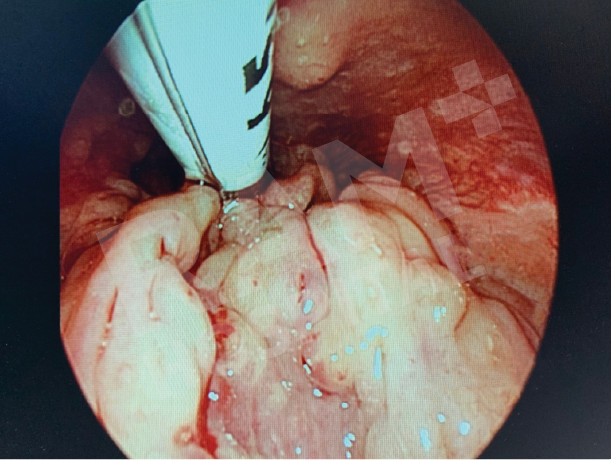

通过口腔内镜辅助,对舌根和会厌部位的肿瘤进行微创手术

通过口腔内镜辅助,对喉部或声带部位的肿瘤进行不用刀的微创手术。

术前 |

术后 |

术后

Source: Photo courtesy of Dr. Puripan Aramawattanapong, Ear, Nose, and Throat Specialist